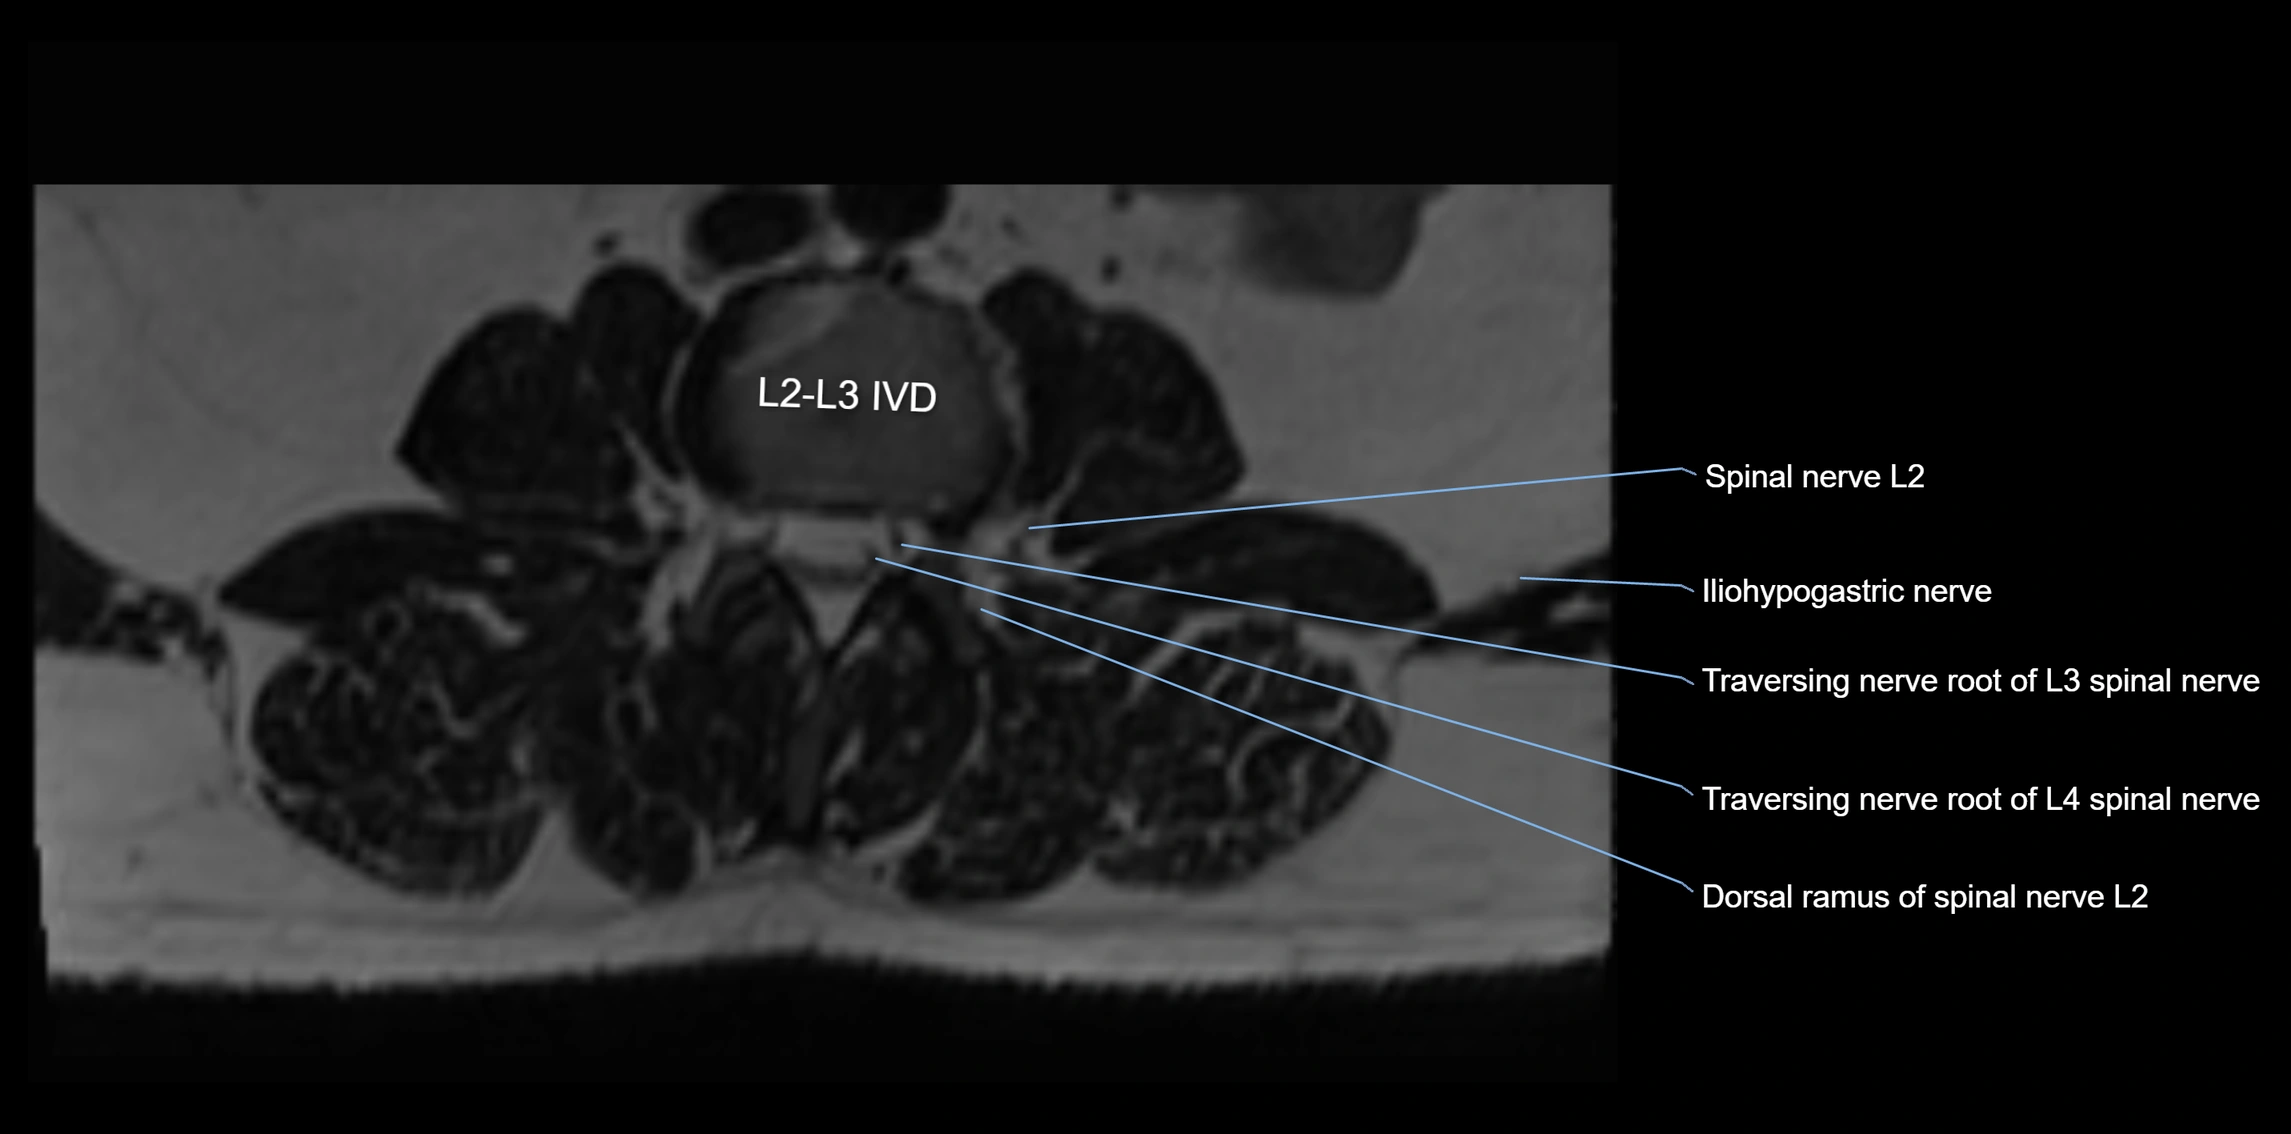

MRI image

image